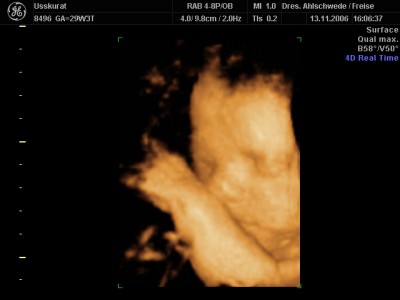

Aufgrund meines Diabetes kann Makrosomie beim Kind entstehen, dass heisst, das Kind wächst schneller als seine Organe. Unsere Lieselotte ist nun an der oberen Grenze, sie ist groß und schwer.... Knapp 42 cm und 2000 g.....

Jetzt muss ich in 2 Wochen wieder hin, vielleicht hatte sie nur gerade einen mächtigen Schub gemacht und beim nächsten Mal pendelt es sich wieder ein. CTG war gut, das Herz blubberte lustig vor sich hin. :wink: Meine FÄ meinte nur, den 26.01. werden wir vielleicht nicht als Termin halten können, im Zweifelsfall wird sie früher geholt, muss man mal abwarten.... :-?

Heute konnte man leider nur eine Hand und das Ohr besonders gut erkennen, stell Euch mal ein Bild vom letzten Mal rein, ist ja auch noch ganz frisch. :D

Dateianhänge

131106_3.JPG

Wow,Claerchen,ist das ein schööönes Bild! :dance: :dance: :dance: Ich bin ja immer wieder begeistert,wie deutlich das Alles heutzutage ist! :prima: Sowas gab's zu meiner Zeit ja nicht..schluchz :cry: .

Claerchen, davon hab ich auch schon gehört,dass Babys von Diabetiker schon größer werden können.. :grübel: Aber es könnte doch auch genau sogut sein,dass Lieselottchen einfach nur ein großes Kind ist..schließlich liegt sie ja in der Norm! :jaja: ...Sie ist einfach ein strammes Mädel!! :dance: Und das Bild fasziniert mich echt total...zu süüüüüüßßßß..will auch haben.. :cry: